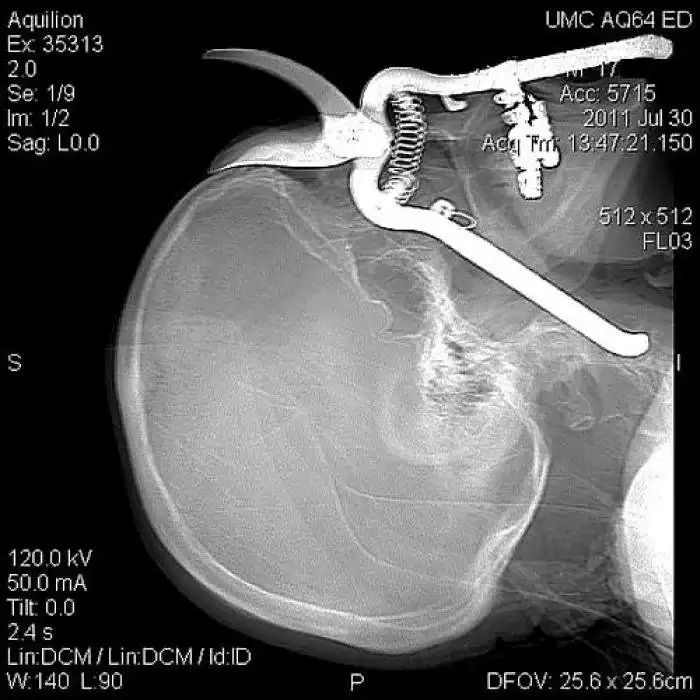

На рентгеновских снимках людей порой можно обнаружить самые необычные предметы, которые находятся в их теле.